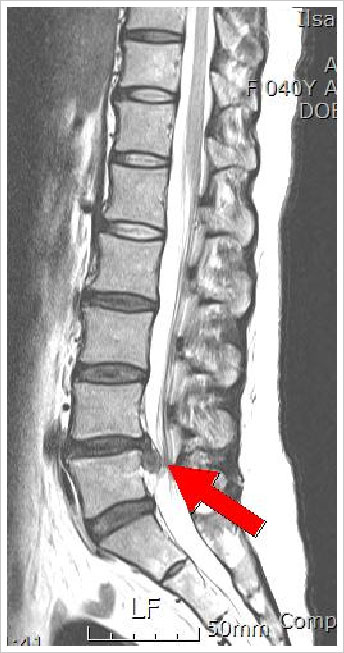

£ª ¿äÃߺÎÀ§ - ¿äÃßÀÇ Ãß°£ÆÇ Å»ÃâÁõÀÌ ÀÖ´Â ´ëºÎºÐÀÇ

»ç¶÷µéÀÌ ½ÉÇÑ ÇÏÁö ÅëÁõÀ» È£¼ÒÇÕ´Ï´Ù. ÀÌ ÅëÁõÀº Á°ñ½Å°æÀÇ ¾Ð¹Ú¿¡ ÀÇÇØ ¹ß»ýÇÏ´Â ÅëÁõÀ¸·Î

Á°ñ½Å°æÅëÀ̶ó°í ÈçÈ÷ ¸»ÇÕ´Ï´Ù. ÀÌ ÅëÁõÀº ´ë°³ Ç㸮¿¡¼ ½ÃÀÛµÇ¾î ¾ûµ¢ÀÌ, ³ÒÀû´Ù¸®¸¦

Áö³ª Á¾¾Æ¸®ÂÊÀ¸·Î »¸ÃÄ ³»·Á¿É´Ï´Ù. Á°ñ½Å°æÅëÀº ÀüÇüÀûÀÎ °æ¿ì ±âħ, Àçä±â µî¿¡ ÀÇÇØ

¾Çȵ˴ϴÙ. ½¬¸é ÁÁ¾ÆÁö°í ¿îÀüÇϰųª ¹°°ÇÀ» µé¾î¿Ã¸± ¶§ ¾Çȵ˴ϴÙ. °¨°¢ÀÌ ¹«µð¾î Áö°Å³ª

Àú¸° ´À³¦, ±ÙÀ°ÀÇ À§¾à µîÀÌ ³ÒÀû´Ù¸®³ª Á¾¾Æ¸® ÂÊ¿¡ ³ªÅ¸³ª±âµµ ÇÕ´Ï´Ù. µå¹°Áö¸¸ º¸´Ù

½ÉÇÑ Ãß°£ÆÇ Å»ÃâÁõÀÇ °æ¿ì ½Å°æÀÌ ±¤¹üÀ§ÇÏ°Ô ¾Ð¹ÚµÇ¾î Àå, ¹æ±¤ ±â´É¿¡ Àå¾Ö°¡ »ý±â°í

»ý½Ä±â ºÎÀ§ ¹Ì ¹× ¾ûµ¢ÀÌ, ³ÒÀû´Ù¸® Ç㸮 ºÎÀ§ °¨°¢ÀÌ ÀúÇϵDZ⵵ ÇÕ´Ï´Ù. |